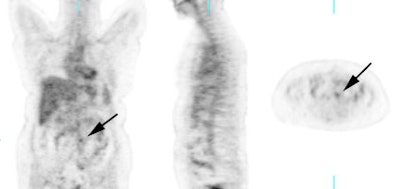

Recurrent ovarian cancer: 58 year old female with a history of treated recurrent ovarian carcinoma. Follow-up CT scan showed a left para-aortic soft tissue mass which had remained stable for 3 months. PET FDG exam revealed uptake of tracer in the left para-aortic mass, compatible with metastatic retroperitoneal lymphadenopathy (top row of images). Radiation therapy was instituted and a follow-up PET exam after completion of therapy revealed marked interval decrease in tracer uptake (black arrow). There is some faint residual uptake evident. Case courtesy North Texas Clinical PET Institute and CTI. |